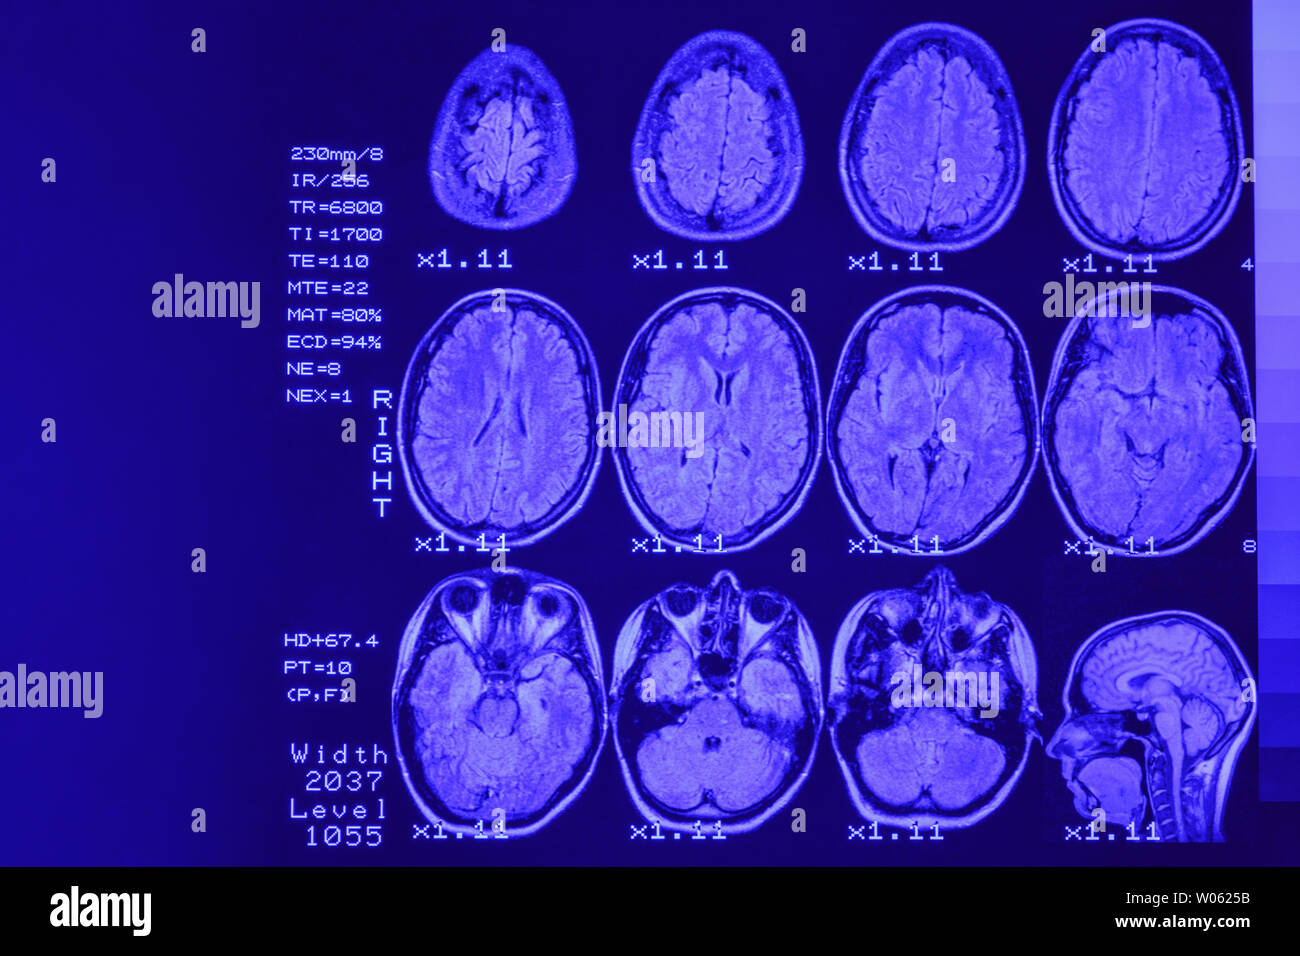

MRI scan or magnetic resonance image of head and brain scan. The result is an MRI of the brain with values and numbers with blue backlight. Stock Photohttps://www.alamy.com/image-license-details/?v=1https://www.alamy.com/mri-scan-or-magnetic-resonance-image-of-head-and-brain-scan-the-result-is-an-mri-of-the-brain-with-values-and-numbers-with-blue-backlight-image258288951.html

MRI scan or magnetic resonance image of head and brain scan. The result is an MRI of the brain with values and numbers with blue backlight. Stock Photohttps://www.alamy.com/image-license-details/?v=1https://www.alamy.com/mri-scan-or-magnetic-resonance-image-of-head-and-brain-scan-the-result-is-an-mri-of-the-brain-with-values-and-numbers-with-blue-backlight-image258288951.htmlRFW0625B–MRI scan or magnetic resonance image of head and brain scan. The result is an MRI of the brain with values and numbers with blue backlight.